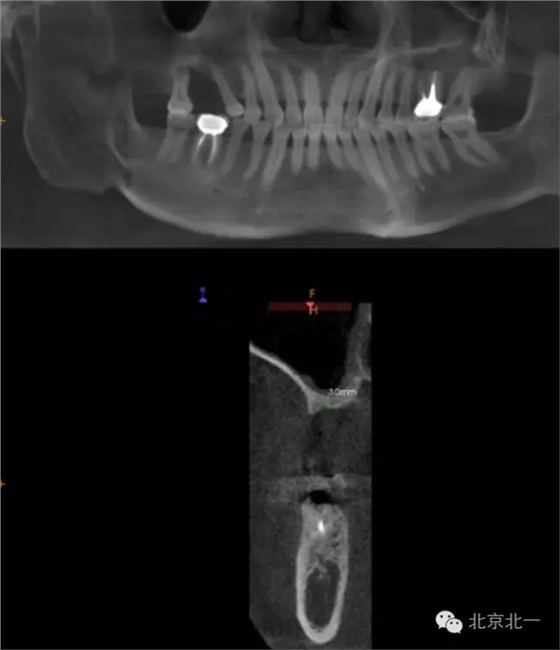

CBCT顯示,骨寬度可,骨高度不足,月3mm。頜間距離增大。

圖三:骨高度3mm.